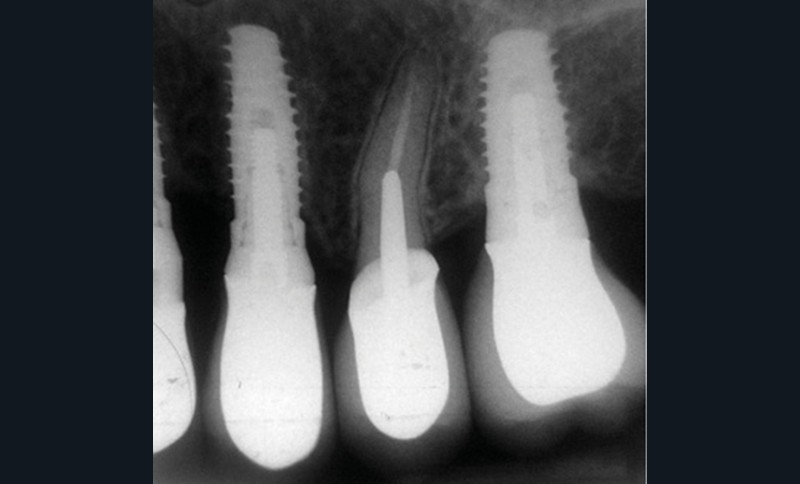

En mars 2016, la patiente se plaint d’une sensibilité sur la 25 et on note cliniquement une inflammation gingivale associée à un décalage apical du rebord marginal et de la ligne muco-gingivale en comparaison de leur situation visualisée au niveau des coiffes supra-implantaires. La couronne clinique est réduite et une infraposition avec une inocclusion d’environ 2 mm par rapport au plan d’occlusion et aux dents antagonistes est également notée (fig. 2 à 4). Un saignement au sondage ainsi qu’une poche de 5 mm en distal sont constatés. Le test de percussion est positif. Les tissus péri-implantaires adjacents ne présentent aucun signe de mucosite.

La radiographie péri-apicale au long cône confirme, sur la 25, un élargissement desmodontal, notamment en distal, des niveaux osseux mésio-distaux réduits par rapport aux clichés de contrôle précédents (les radiographies sont réalisées avec une technique parallèle avec des angulateurs de Rinn non personnalisés), un apex radiculaire normal et des niveaux osseux stables sur les implants adjacents (fig. 5). Le cisaillement systématique du fil dentaire lors de son passage confirme des points de contact très étroits entre 24, 25 et 26.